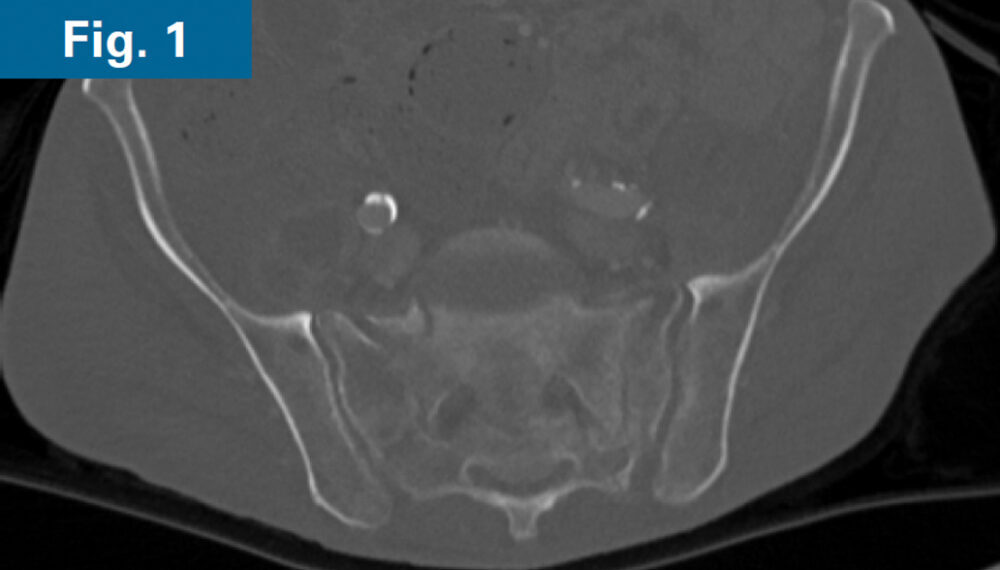

• 62 y/o male with COPD and 1 month old sacral U-type fracture after motorcycle crash (Figs. 1 and 2)

• Comminution and displacement of the right side component of his sacral U-type fracture significantly decreased the osseous corridor for placement of trans-sacral style screw in S1 requiring an iFuse TORQ® implant to provide sufficient fixation